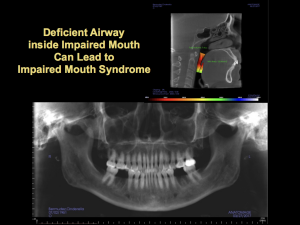

Serious risks and consequences can come from staying inside the traditional dental box, using only panoramic x-rays, and study casts to determine irreversible treatment. Two teeth were treated and lost without considering the possible causes. The dentist offered to credit CB for the money she paid for the failed dentistry and extractions.

deficient airway

Consider the airway and its effect on the dental pulp before starting restorative or endodontic treatment.

Cone beam CT imaging showed a narrow airway with a high risk of collapse during sleep. Pulpal angina is the dental version of a myocardial infarction, and the pain comes from oxygen starvation. Chronic oxygen deficiency also leads to muscle trigger points that are regular features of chronic pain in TMJ dysfunction.